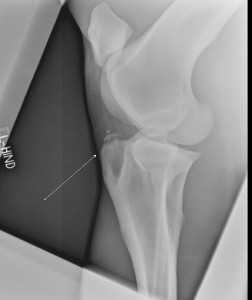

CSA2